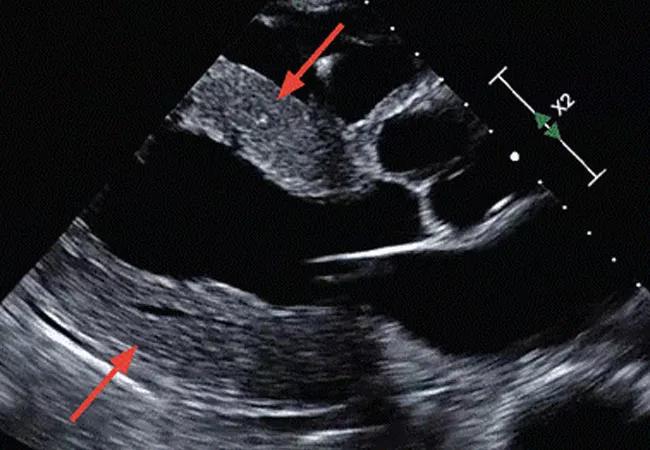

Echocardiography showed a left ventricular ejection fraction of 55% and concentric left ventricular wall hypertrophy with a wall thickness of 15 mm (Figure 1). Echocardiography with strain imaging to evaluate function of the myocardium revealed longitudinal impairment with apical sparing, i.e., the “cherry-on-top” appearance. There was no pericardial effusion.

Parasternal long-axis view on echocardiography.

Figure 1. Parasternal long-axis view on echocardiography demonstrates diffuse concentric left ventricular hypertrophy (arrows).